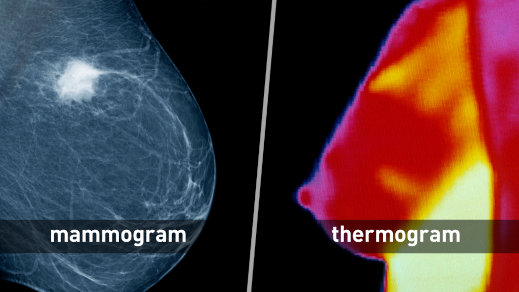

באותו פוסט ממשיך אבני מסורת ארוכה של פרסום המלצות שנוגדות את הידע הקיים ומסכנות את בריאות הציבור. הוא קורא לנשים לסרב לממוגרפיה כי "יש לנו כלים נהדרים" לאבחון מוקדם של סרטן, כגון תֶּרְמוֹגְרַפְיָה – בדיקה שמשתמשת במצלמת תת-אדום כדי להציג הבדלי טמפרטורה בסמוך לעור.

אולם משרד הבריאות של קנדה, Health Canada, מזהיר שאין כל ראיה ליעילותה של תרמוגרפיה בזיהוי מוקדם של סרטן שד, ומציין שממוגרפיה היא הבדיקה היחידה שהודגמה כבטוחה וכיעילה לביצוע בדיקות סקר לגילוי מוקדם של סרטן השד. גם מינהל המזון והתרופות של ארצות הברית (ה-FDA) מזהיר שאין ראיות ליעילות של תרמוגרפיה כבדיקה לזיהוי סרטן במקום ממוגרפיה, ושמי שתסתפק רק בבדיקה זו, כתחליף לבדיקת ממוגרפיה, עלולה "להחמיץ את ההזדמנות לגלות את סרטן השד בשלביו המוקדמים ביותר", כשעוד ניתן לטפל בו בקלות יחסית.